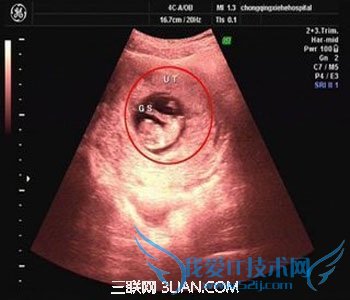

¡¡¡¡Èç¹û×¼µùÂèÃÇÏëÖªµÀ»³ÔÐ50ÌìÔÐÄÒ´óС±ê×¼ÖµµÄ»°£¬ÎÒÃÇ¿ÉÒԲο¼Ò»ÏÂÔÐÄÒ´óС¶ÔÕÕ±í£¬ÔÚÔÐÄÒ´óС¶ÔÕÕ±íÖУ¬ÎÒÃÇ¿ÉÒÔÇå³þµØ¿´µ½»³ÔÐÿһʱÆÚµÄÔÐÄÒ´óСµÄ±ê×¼Öµ¡£ÏÖÔÚ½«ÔÐÄÒ´óС¶ÔÕÕ±í¸½ÉÏ¡£

¡¡¡¡4ÖÜ£ºÌ¥¶ùÖ»ÓÐ0.2ÀåÃס£Êܾ«ÂѸÕÍê³É×Å´²£¬ÑòĤǻ²ÅÐγɣ¬Ìå»ýºÜС¡£³¬Éù»¹¿´²»ÇåÈÑÉï¼£Ïó¡£

¡¡¡¡5ÖÜ£ºÌ¥¶ù³¤µ½0.4ÀåÃ×£¬½øÈëÁËÅßÌ¥ÆÚ£¬ÑòĤǻÀ©´ó£¬ÔʼÐÄѪ¹Ü³öÏÖ£¬¿ÉÓв«¶¯¡£B³¬¿É¿´¼ûС̥ÄÒ£¬Ì¥ÄÒÔ¼Õ¼¹¬Ç»²»µ½1/4£¬»ò¿É¼û̥ѿ¡£

¡¡¡¡6ÖÜ£ºÌ¥¶ù³¤µ½0.85ÀåÃ×£¬Ì¥¶ùÍ·²¿¡¢ÄÔÅÝ¡¢¶îÃæÆ÷¹Ù¡¢ºôÎü¡¢Ïû»¯¡¢Éñ¾µÈÆ÷¹Ù·Ö»¯£¬B³¬Ì¥ÄÒÇåÎú¿É¼û£¬²¢¼û̥ѿ¼°Ì¥ÐÄÌø¡£

¡¡¡¡7ÖÜ£ºÌ¥¶ù³¤µ½1.33ÀåÃ×£¬ÅßÌ¥ÒѾßÓÐÈ˳ûÐΣ¬Ìå½ÚÒÑÈ«²¿·Ö»¯£¬ËÄÖ«·Ö³ö£¬¸÷ϵͳ½øÒ»²½·¢Óý¡£B³¬Çå³þ¿´µ½Ì¥Ñ¿¼°Ì¥ÐÄÌø£¬Ì¥ÄÒÔ¼Õ¼¹¬Ç»µÄl/3¡£

¡¡¡¡8ÖÜ£ºÌ¥¶ù³¤µ½1.66ÀåÃ×£¬Ì¥ÐÎÒѶ¨£¬¿É·Ö³ö̥ͷ¡¢Ìå¼°ËÄÖ«£¬Ì¥Í·´óÓÚÇû¸É¡£B³¬¿É¼ûÌ¥ÄÒÔ¼Õ¼¹ÙÇ»1/2£¬Ì¥¶ùÐÎ̬¼°Ì¥¶¯Çå³þ¿É¼û£¬²¢¿É¿´¼ûÂÑ»ÆÄÒ¡£

¡¡¡¡9ÖÜ£ºÌ¥¶ù³¤µ½2.15ÀåÃ×£¬Ì¥¶ùÍ·´óÓÚÌ¥Ì壬¸÷²¿±íÏÖ¸üÇåÎú£¬Í·Â¿ªÊ¼¸Æ»¯¡¢Ì¥ÅÌ¿ªÊ¼·¢Óý¡£B³¬¿É¼ûÌ¥ÄÒ¼¸ºõÕ¼Âú¹¬Ç»£¬Ì¥¶ùÂÖÀª¸üÇåÎú£¬Ì¥ÅÌ¿ªÊ¼³öÏÖ¡£

¡¡¡¡10ÖÜ£ºÌ¥¶ù³¤µ½2.83ÀåÃ×£¬Ì¥¶ù¸÷Æ÷¹Ù¾ùÒÑÐγɣ¬Ì¥Å̳ûÐÎÐγɡ£B³¬¿É¼ûÌ¥ÄÒ¿ªÊ¼Ïûʧ£¬ÔÂÑ¿ÐÎÌ¥Å̿ɼû£¬Ì¥¶ù»îÔ¾ÔÚÑòË®ÖÐ ¡£

¡¡¡¡11ÖÜ£ºÌ¥¶ù³¤µ½3.62ÀåÃ×£¬Ì¥¶ù¸÷Æ÷¹Ù½øÒ»²½·¢Óý£¬Ì¥ÅÌ·¢Óý¡£B³¬¿É¼ûÌ¥ÄÒÍêÈ«Ïûʧ£¬Ì¥ÅÌÇåÎú¿É¼û¡£